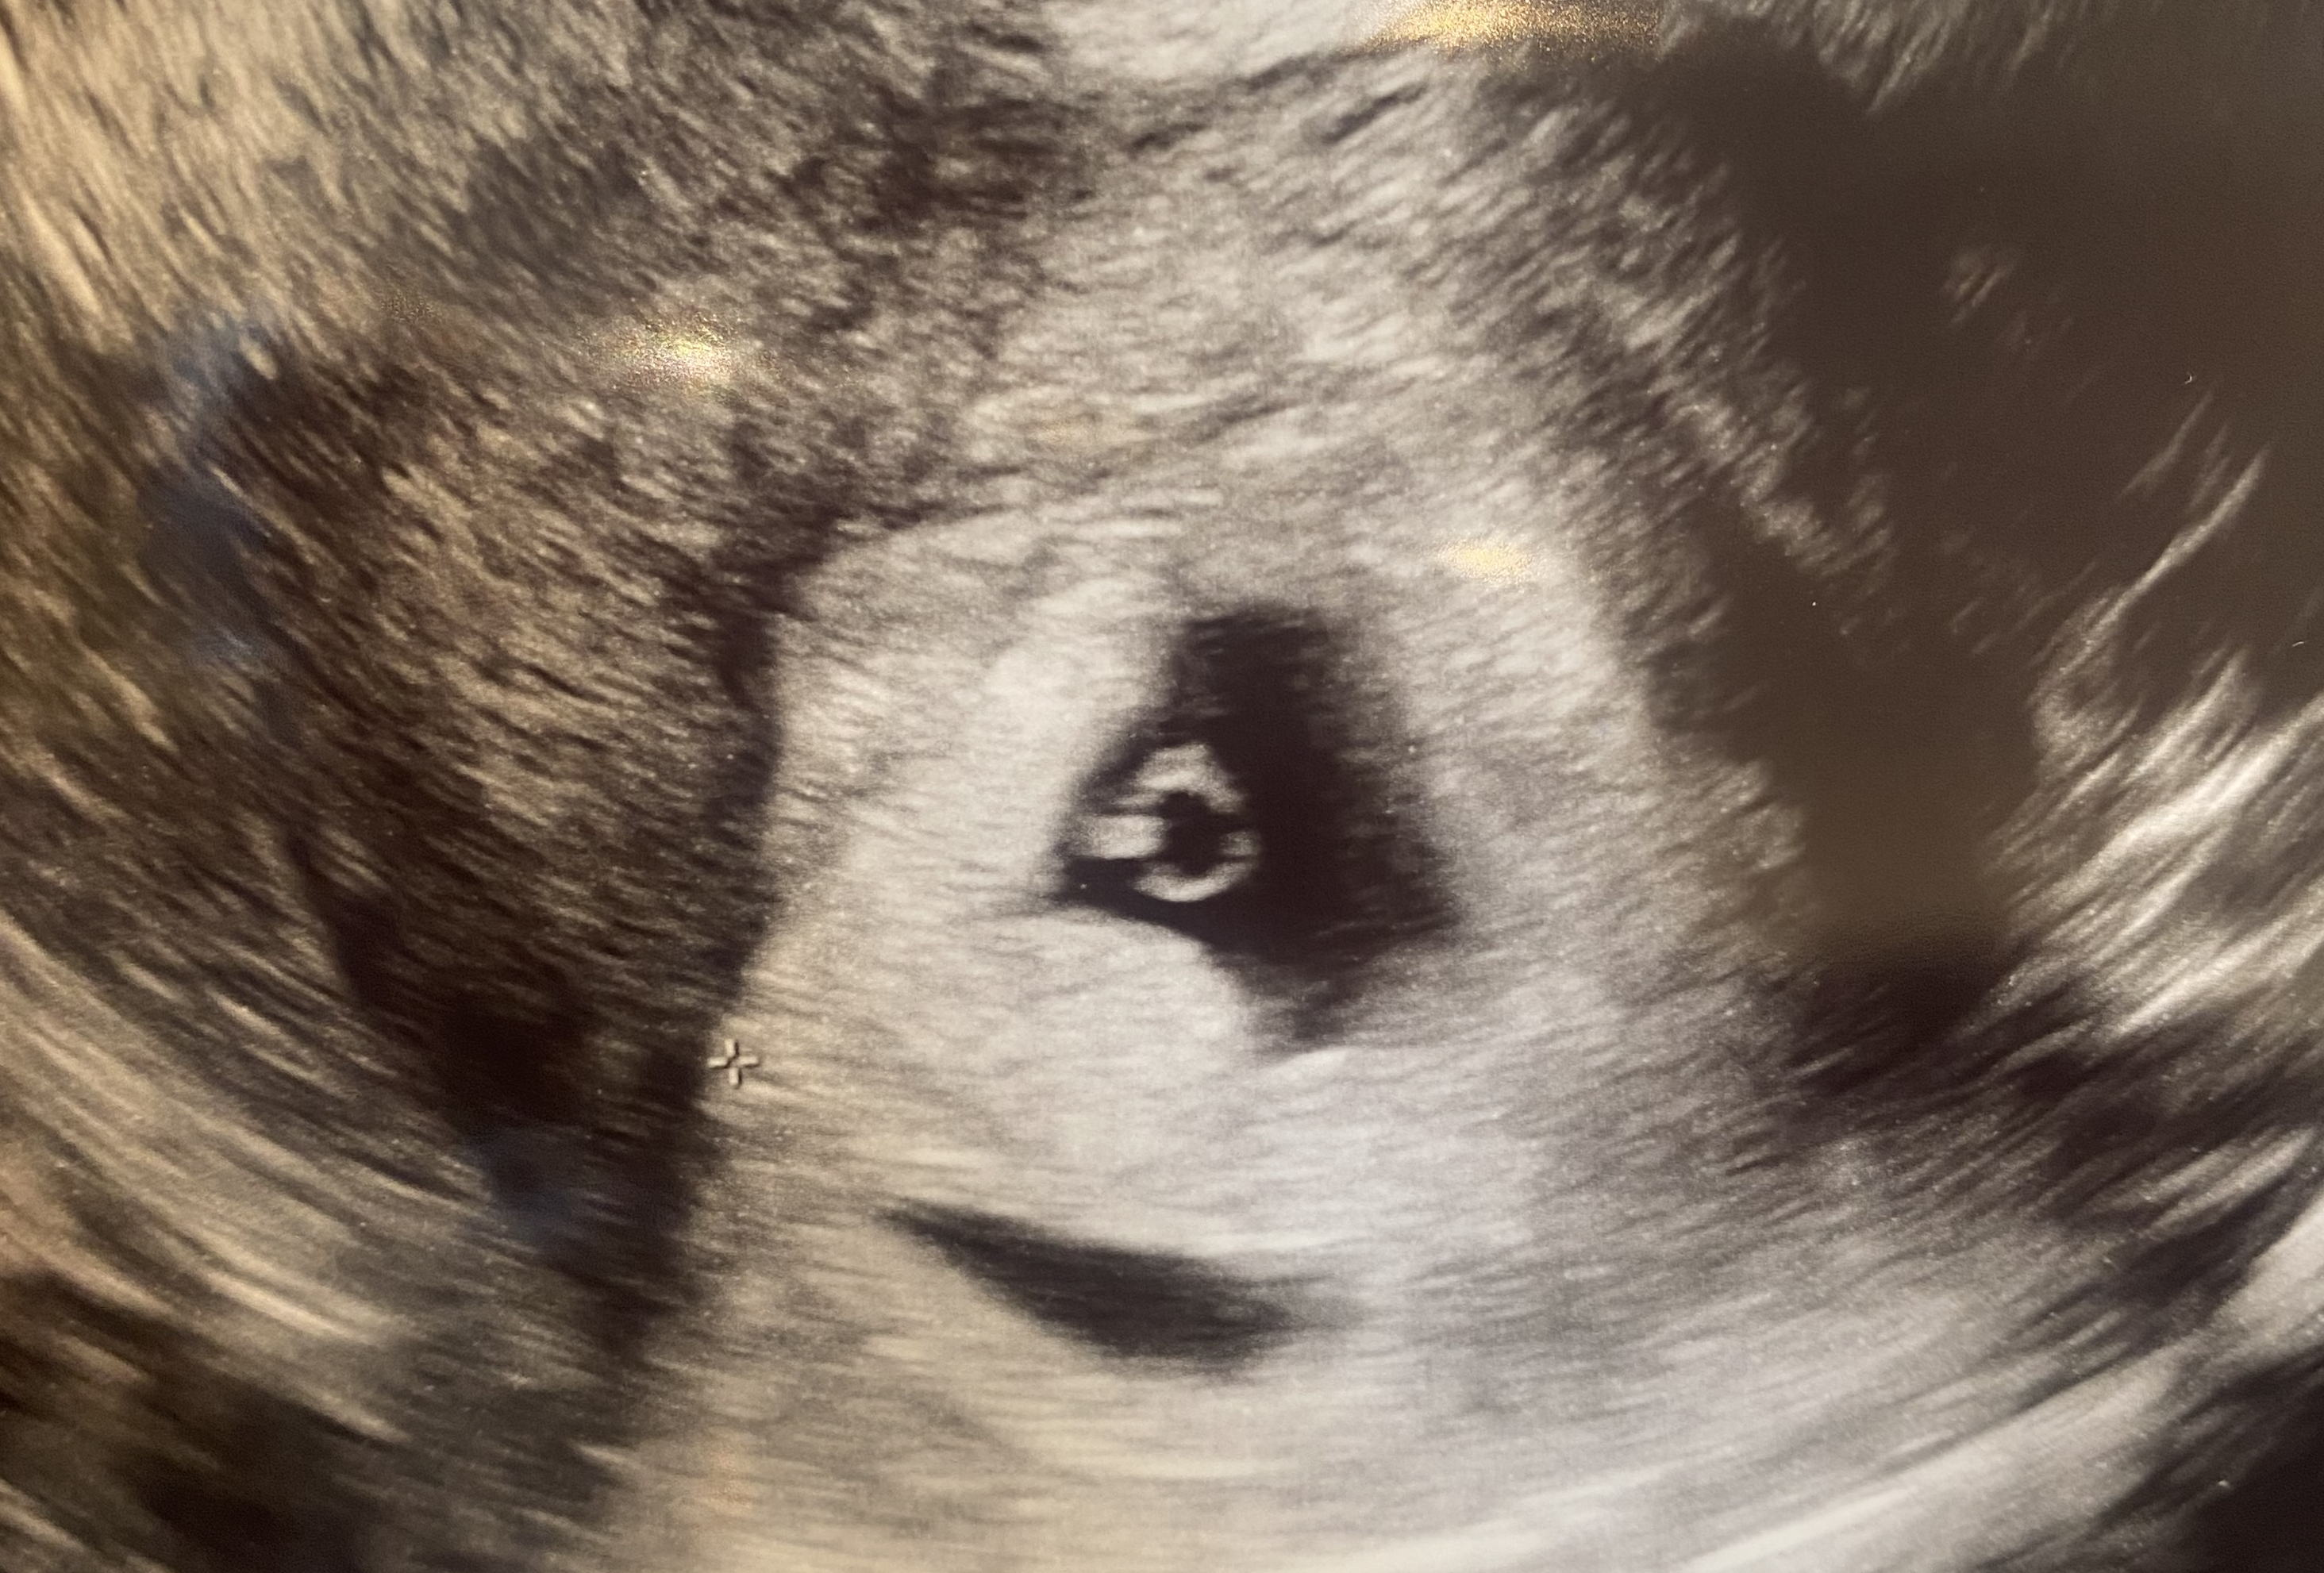

| 가슴 떨리는 임신 이야기를 공유해 주세요. | 이유정 원장님을 믿고 치료를 이어가던 중, 운이 좋게 아기천사가 찾아와 주었습니다. 임신 사실을 알았을 때가 가장 기뻤고, 그 순간의 감동은 지금도 잊을 수 없습니다. |

| 치료 도중 느꼈던 가장 기뻤던 순간과 절망적인 것들은 무엇인가요? 잊지 못할 경험이 있나요? | 임신 사실을 처음 알았을 때가 가장 기뻤습니다. 다만 6주에서 8주 사이 하혈이 있어 걱정이 컸지만, 결국 아기를 건강하게 지킬 수 있어 더욱 감사한 기억으로 남아 있습니다. |